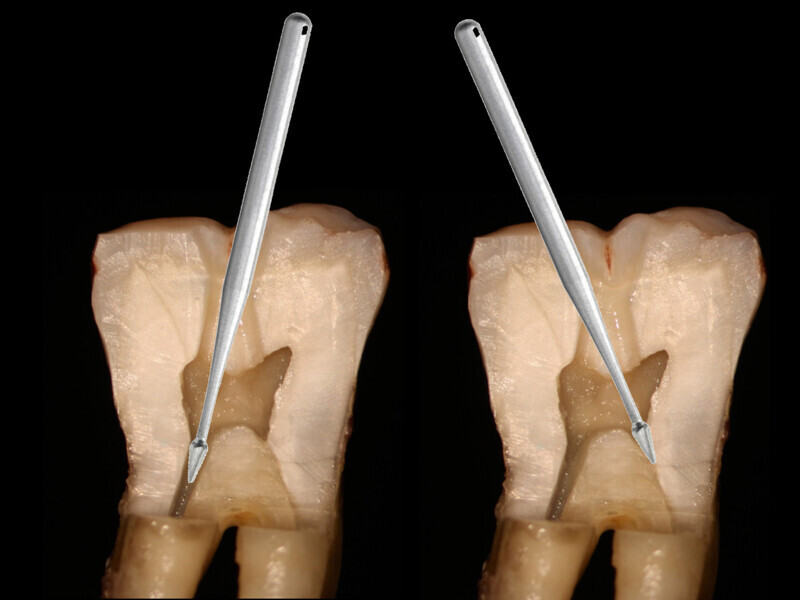

Fig. 2: Traditional endodontic access with an attempt at straight line entrance into the canal orifice typically follows a vertical path necessitating more coronal tooth structure removal.

Fig. 3: An orifice-directed access conserves more tooth structure as it follows the direction of the canal, resulting in a smaller access opening and preservation of critical tooth.